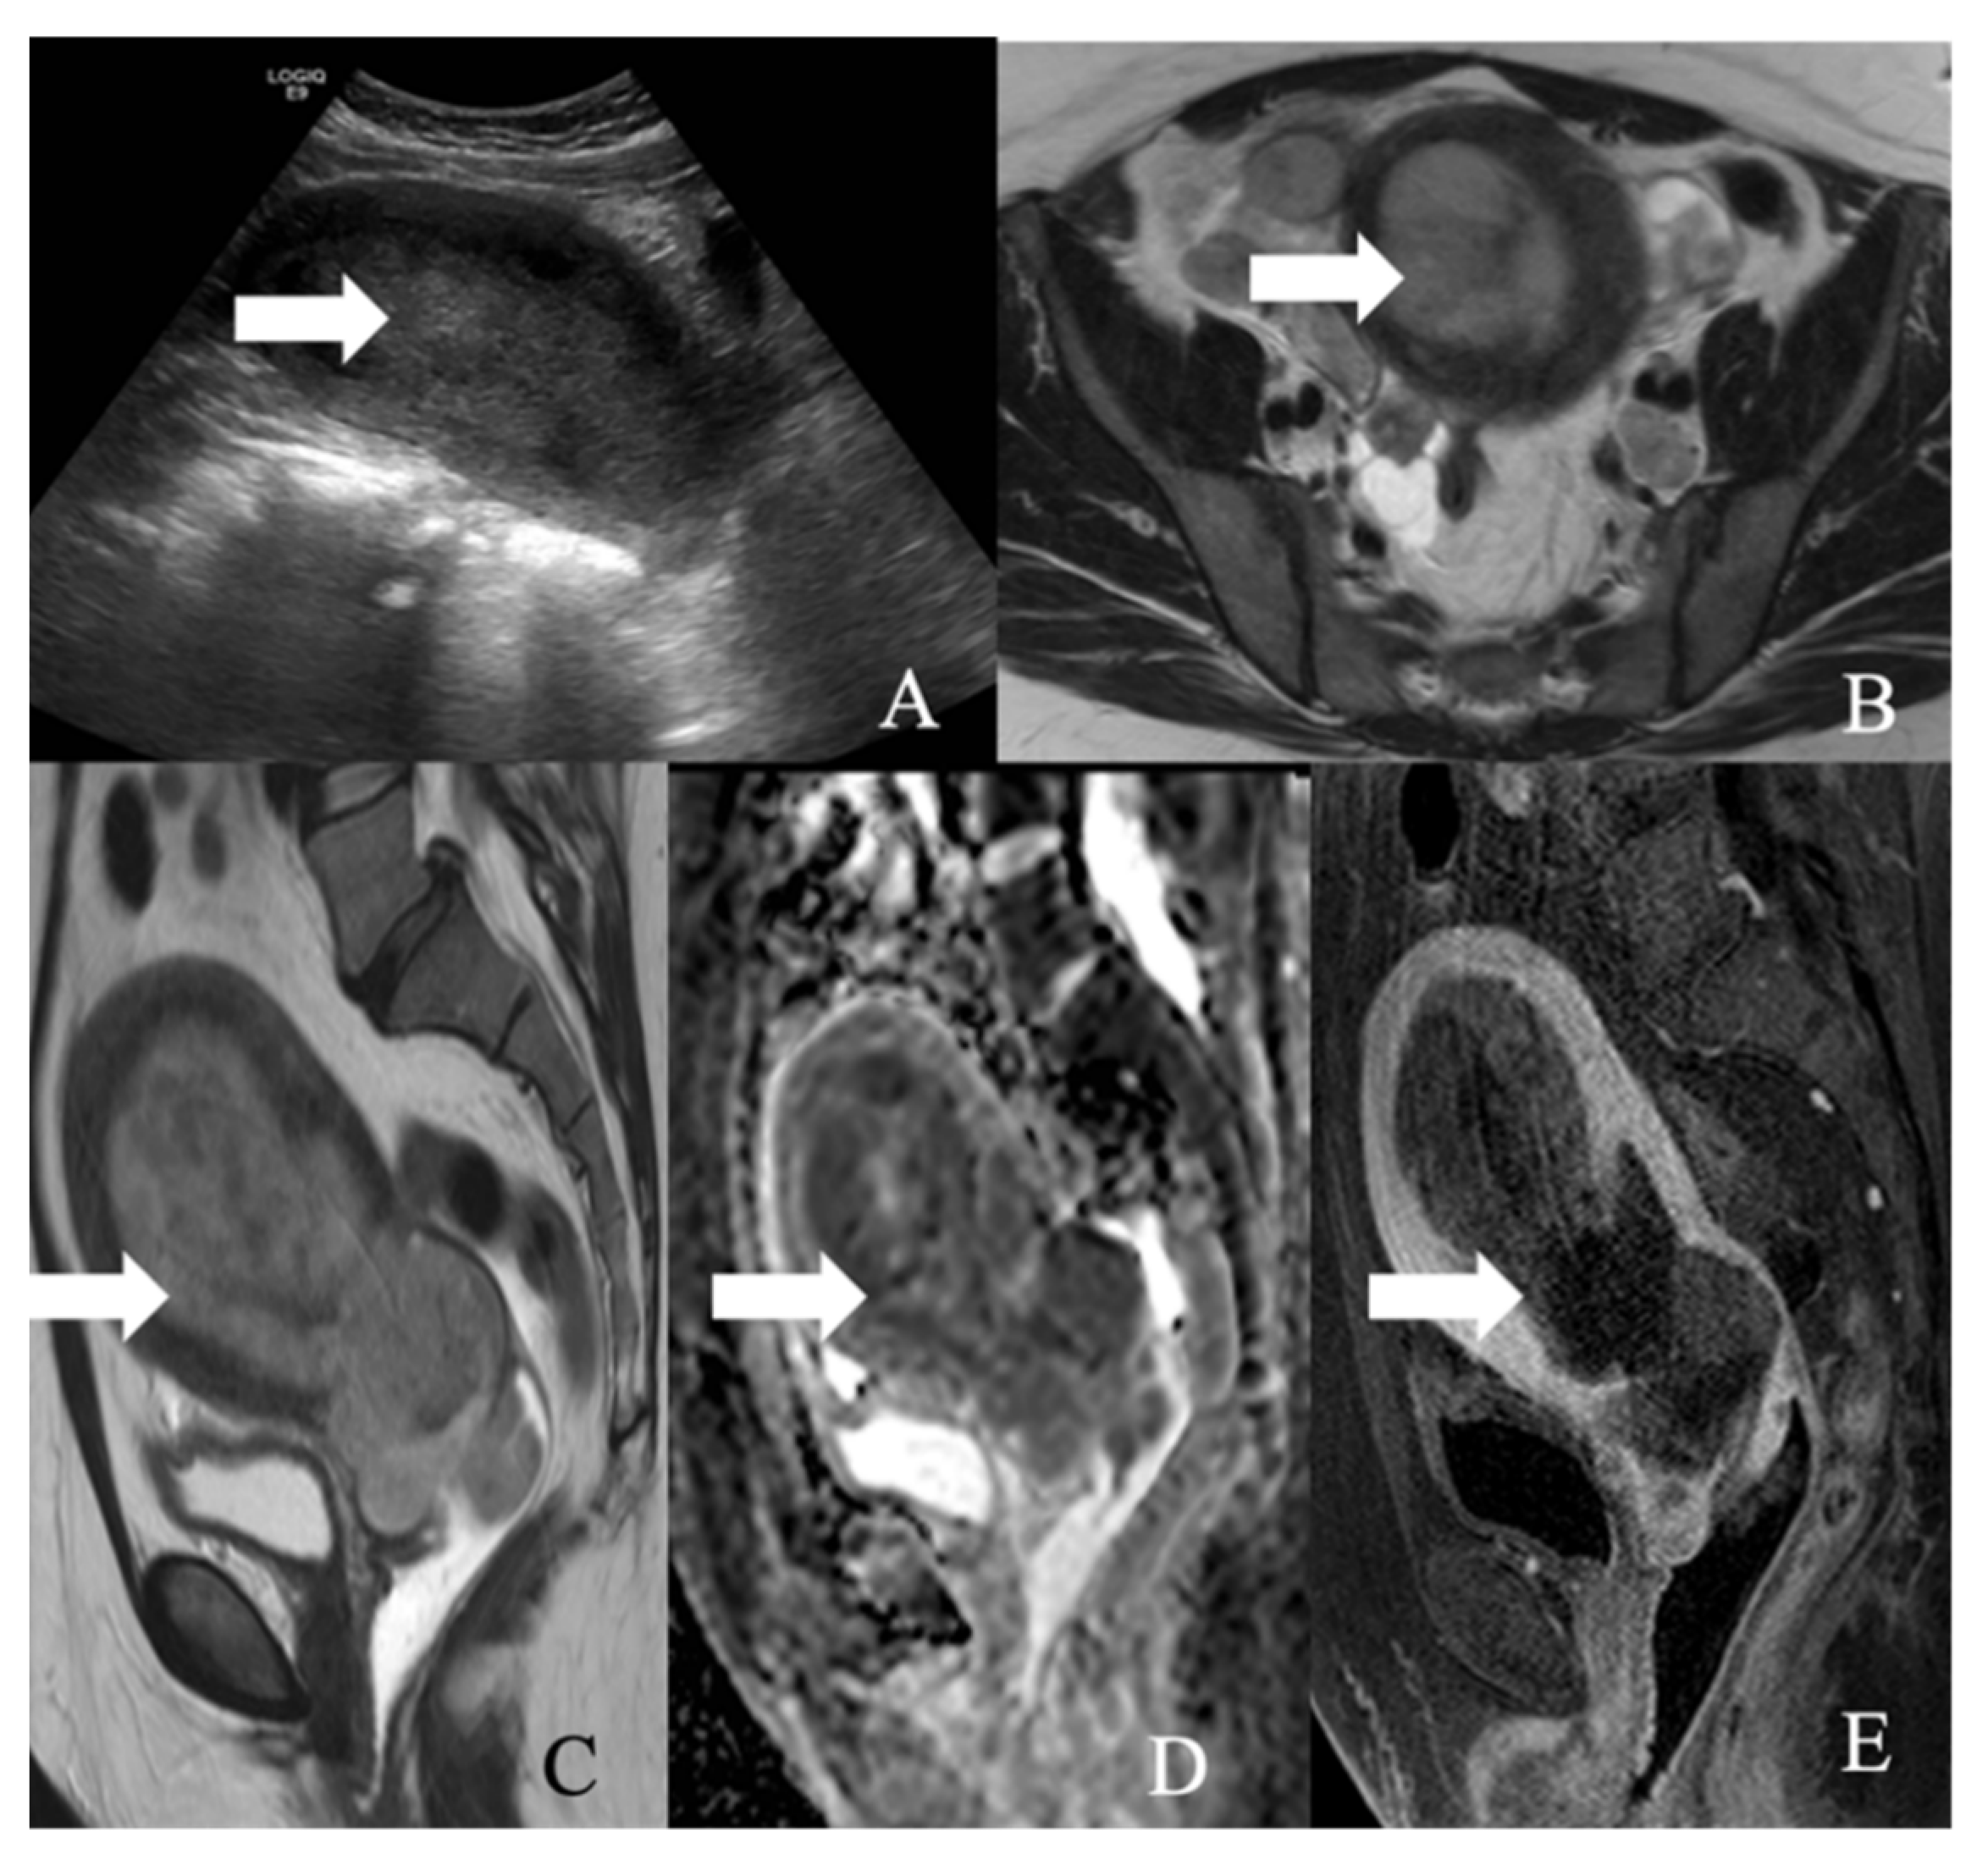

Figure 5. 2018 FIGO staging system for cervical cancer. Stage I, confined to the cervix. Stage IA, ≤5 mm depth. Stage IA1, ≤3 mm depth. Stage IA2, 3 mm and ≤5 mm depth. Stage IB, >5 mm depth. Stage IB1, ≤2 cm maximum diameter. Stage IB2, >2 cm and ≤4 cm maximum diameter. Stage IB3, >4 cm maximum diameter. Stage II, beyond the uterus but not involving the lower one-third of the vagina or pelvic sidewall. Stage IIA, upper two-thirds of the vagina. Stage IIA1, upper two-thirds of the vagina and ≤4 cm. Stage IIA2, Upper two-thirds of the vagina and >4 cm. Stage IIB, parametrial invasion. Stage III, lower vagina, pelvic sidewall, ureters, and lymph nodes. Stage IIIA, lower one-third of the vagina. Stage IIIB, pelvic sidewall. Stage IIIC, pelvic, and para-aortic lymph node involvement. Stage IIIC1, pelvic lymph node involvement. Stage IIIC2, para-aortic lymph node involvement. Stage IV, adjacent and distant organs. Stage IVA, rectal or bladder involvement. Stage IVB, distant organs outside the pelvis.